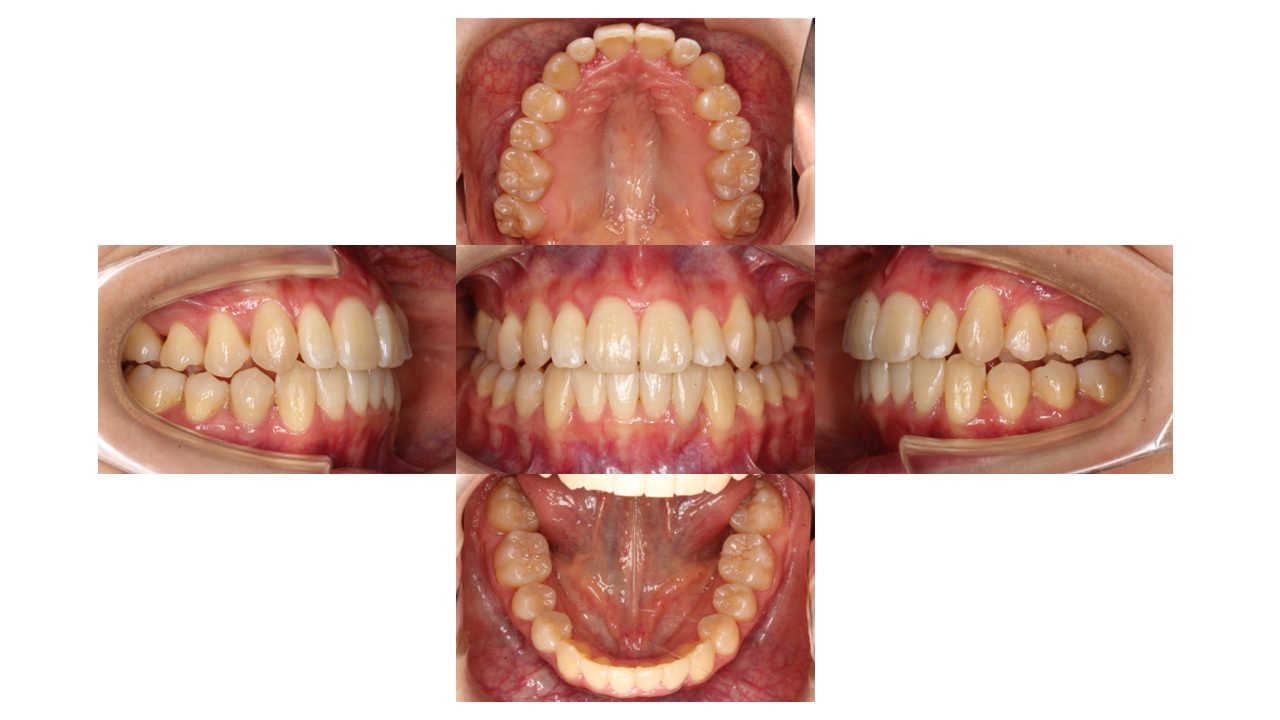

3年4ヶ月経過の口腔内の状態です。

上下前歯の凸凹が改善されたとご満足いただけました。

| 年齢層 | 20代 |

| 性別 | 女性 |

| 主訴 | 上下前歯の凸凹 |

| 治療費用 | 検査・診断:税込38,500円/マウスピース矯正(インビザライン):税込990.000円 |

| 治療期間 | 3年4ヶ月(29回) |

| 抜歯 | 無(非抜歯) |

| 矯正の装置 | マウスピース矯正(インビザライン) |

| 副作用、リスク | 歯肉退縮,歯根吸収,疼痛,咬合の違和感,装置の違和感,虫歯,歯肉炎 |